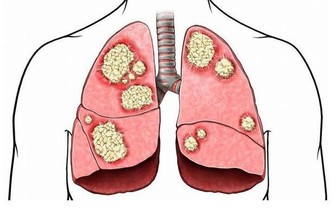

我們可以從聲音洪亮不洪亮看出一個人的肺部健康情況。

如果說你的肺氣十分充足的話,那麼聲音就會十分的響亮。肺比較不少的話就會特別的無力。